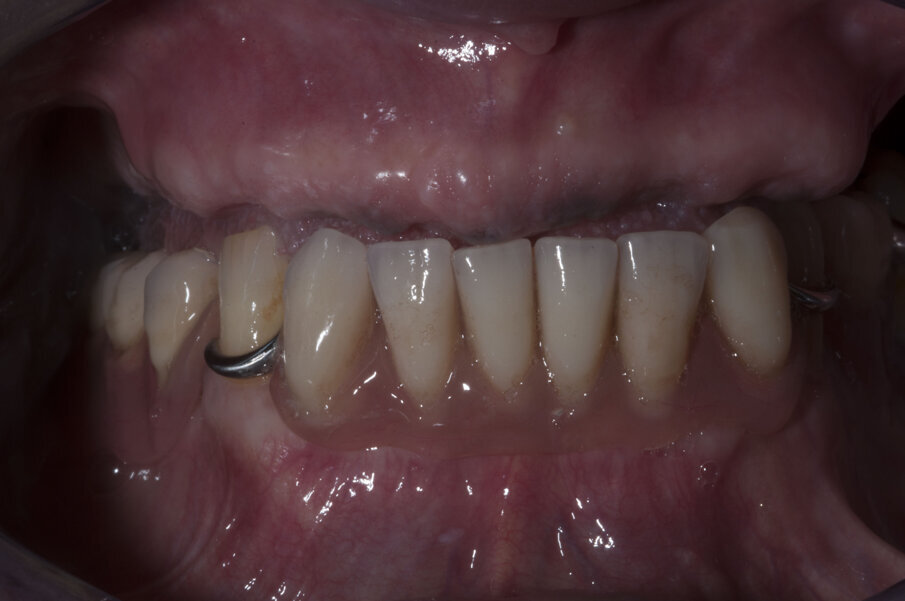

Il primo passo per riabilitare la paziente è stato comunque la sostituzione della protesi totale con una nuova più congrua, questo ha portato alla correzione sia della classe scheletrica non corretta che della VDO, fonte di disagio e sofferenza. L’esame extra-orale evidenziava questo dettaglio e come questo influenzasse il sorriso della paziente (Figg. 5-7).